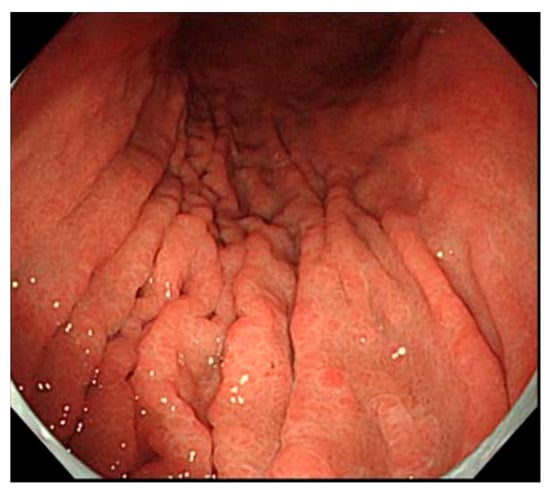

4.2.1. Findings via White Light Observation

- Maruyama, Y.; Kageoka, M. Diagnosis of Type A gastritis. Stomach Intest. 2016, 51, 77–86. (In Japanese) [Google Scholar]

- Kamada, T.; Maruyama, Y.; Monobe, Y.; Haruma, K. Endoscopic features and clinical importance of autoimmune gastritis. Dig. Endosc. 2021, 21, 14175. [Google Scholar] [CrossRef]

- Maruyama, Y.; Yoshii, M.; Kageoka, M. Features of magnifying endoscopic findings in type A gastritis. Stomach Intest. 2018, 53, 1516–1521. (In Japanese) [Google Scholar]